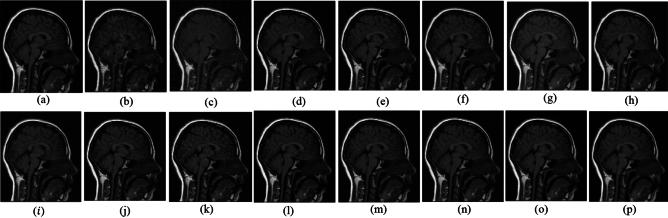

Medical imaging systems such as computed tomography (CT) and magnetic resonance imaging (MRI) are vital tools in clinical diagnosis and treatment planning. However, these modalities are inherently susceptible to Gaussian noise introduced during image acquisition, leading to degraded image quality and impaired visualization of critical anatomical structures. Effective denoising is therefore essential to enhance diagnostic accuracy while preserving fine details such as tissue textures and structural boundaries. This study proposes a robust and efficient denoising framework specifically designed for CT and MRI images corrupted by Gaussian noise. The method integrates a cluster-wise principal component analysis (PCA) thresholding approach guided by the Marchenko-Pastur (MP) law from random matrix theory and a non-local means algorithm. Noise level estimation is achieved globally by analysing the statistical distribution of eigenvalues from noisy image patch matrices and leveraging the MP law to accurately determine the Gaussian noise variance. An adaptive clustering technique is employed to group similar patches based on underlying features such as textures and edges and enables localized denoising operations tailored to heterogeneous image regions. Within each cluster denoising is performed in two stages where initially hard thresholding based on the MP law is applied to the singular values in the SVD domain to obtain a low-rank approximation that preserves essential image content while removing noise-dominated components. Residual noise in the low-rank matrix is then further suppressed through a coefficient-wise linear minimum mean square error LMMSE estimator in the PCA transform domain. Finally, a non-local means algorithm refines the denoised image by computing weighted averages of pixel intensities and prioritizing neighbourhood similarity over spatial proximity to effectively preserve edges and textures while reducing Gaussian noise. Experimental evaluations on CT and MRI datasets demonstrate that the proposed method achieves superior denoising performance while maintaining high structural similarity and perceptual quality compared to existing state-of-the-art approaches. The method demonstrates adaptability noise reduction capability and preservation of anatomical detail that make it well suited for precision critical medical imaging applications.

计算机断层扫描(CT)和磁共振成像(MRI)等医学成像系统是临床诊断和治疗规划中的重要工具。然而,这些模态在图像采集过程中固有地容易受到高斯噪声的影响,导致图像质量下降以及关键解剖结构的可视化受损。因此,有效的去噪对于提高诊断准确性同时保留诸如组织纹理和结构边界等精细细节至关重要。本研究提出了一种强大且高效的去噪框架,专门针对受高斯噪声破坏的CT和MRI图像设计。该方法集成了一种由随机矩阵理论中的马尔琴科 - 帕斯图尔(MP)定律引导的聚类主成分分析(PCA)阈值处理方法和一种非局部均值算法。通过分析噪声图像块矩阵的特征值统计分布并利用MP定律来准确确定高斯噪声方差,实现全局噪声水平估计。采用自适应聚类技术根据纹理和边缘等潜在特征对相似块进行分组,并针对异质图像区域进行局部去噪操作。在每个聚类中,去噪分两个阶段进行,首先在奇异值分解(SVD)域中基于MP定律应用硬阈值处理奇异值,以获得保留基本图像内容同时去除噪声主导成分的低秩近似。然后在PCA变换域中通过系数线性最小均方误差(LMMSE)估计器进一步抑制低秩矩阵中的残余噪声。最后,非局部均值算法通过计算像素强度的加权平均值并优先考虑邻域相似性而非空间邻近性来细化去噪图像,从而在减少高斯噪声的同时有效保留边缘和纹理。对CT和MRI数据集的实验评估表明,与现有的最先进方法相比,所提出的方法在保持高结构相似性和感知质量的同时实现了卓越的去噪性能。该方法展示了适应性降噪能力和解剖细节保留能力,使其非常适合精密关键的医学成像应用。